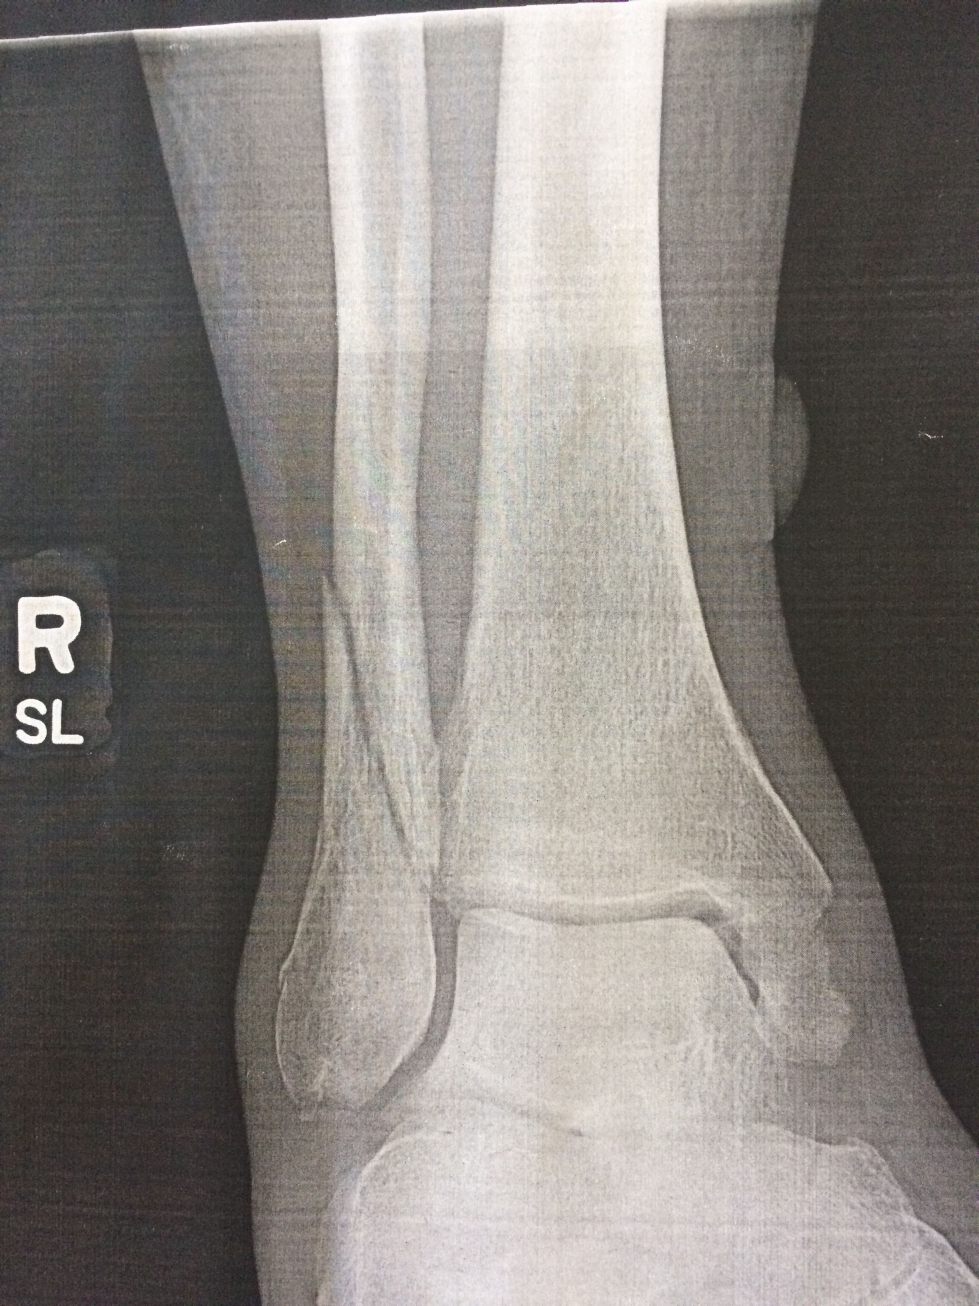

I got home about 2PM on Friday afternoon August 9th. Not a good time to get in to see a doctor. Kay took one look at my ankle and called to schedule an immediate appointment with an orthepedic surgeon. I was getting X-Rays just after 3PM. The tech handed me a printout. Even an amateur could see a clean break in the fibula. Kay also pointed out a problem with the end of the tibia (medial malleolus).